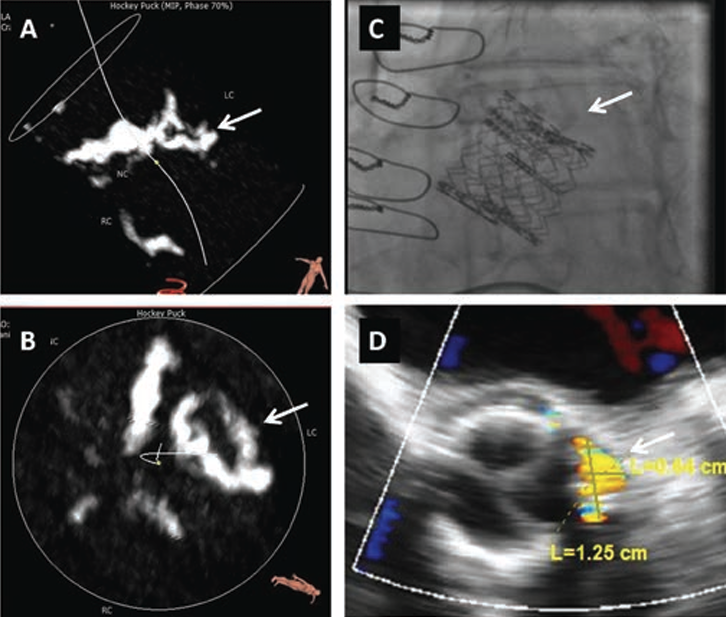

Procedure. All PVL closure procedures were approached in a retrograde manner via the femoral artery and performed as previously described.12 The defect site was crossed with an angled or straight hydrophilic guidewire, supported by an appropriate catheter that directed the wire toward the defect. Once the defect was crossed, the support catheter was advanced across the defect and an Amplatz Extra-Stiff wire (Cook Medical, Inc) was advanced into the left ventricle. Once the stiff wire was in place, an appropriately sized delivery sheath was introduced into the left ventricle to deliver the occluder device. The distal end of the device was deployed below the aortic valve. The device was then pulled back into the defect (Figure 1). All occluder devices deployed in this study were Amplatzer Vascular Plug II (AGA Medical), except one Amplatzer PDA and one Amplatzer muscular VSD used in the SAVR group. Single-antiplatelet therapy with aspirin was administrated to all patients after the procedure, and clopidogrel (1 patient) or warfarin (1 patient) was also prescribed based on the comorbidities.

In 1 post-TAVR case, the patient received a transcatheter valve in a 23 mm Hancock II surgical prosthetic valve (Medtronic). The percutaneous PVL closure for this patient was successfully performed in the space between the surgical valve and TAVR valve (Figure 2). Another patient underwent TV-in-TV at 149 days after the index TAVR procedure because of worsening PVL; however, the PVL remained significant and the patient remained symptomatic. Percutaneous PVL closure was attempted 369 days after the index TAVR, but it was unsuccessful due to difficulty advancing the delivery sheath (Figure 3).

Anatomical features of successful and unsuccessful cases (post-TAVR group). Although there were no significant differences in the echocardiographic assessment between successful and unsuccessful closure cases, computed tomography (CT) assessment showed that there was a trend of greater calcium volume in the aortic valve of unsuccessful cases (937.1 ± 775.0 mm3 vs 313.9 ± 303.0 mm3; P=.14). Further evaluation of calcification in each leaflet corresponding to the PVL revealed a significant difference of calcium volume between unsuccessful vs successful cases (351.4 ± 205.1 mm3 vs 121.8 ± 111.7 mm3, respectively; P=.049). Aortic root angles, which can affect the ability to back up an advanced catheter, were almost identical in both groups (46.0 ± 2.9° vs 36.2 ± 12.0°; P=.15) (Table 4).

Although percutaneous PVL closure definitely has a role in the TAVR era, it seems to be more challenging compared with the post-SAVR patients in our study. During TAVR, the irregular surface of the native calcified aortic valve leaflets are compressed between the wall of the aortic root and the expanded prosthetic valve stent frame. This creates resistance, and the occluder sheath and device are not able to cross an eccentric space between the calcified native leaflet and the stent of the valve. This hypothesis is supported by our observation that we had problems in advancing delivery catheters in all unsuccessful cases, although wires initially did cross. Moreover, the calcium burden of the corresponding leaflets was greater in these cases (351.4 ± 205.1 mm3 in unsuccessful cases vs 121.8 ± 111.7 mm3 in successful cases; P=.049), as demonstrated in Figure 4. This is in contrast to the post-SAVR group, in which all percutaneous PVL closures were performed successfully. The SAVR procedure removes the native leaflet, and the PVL site is therefore a much smoother surface.